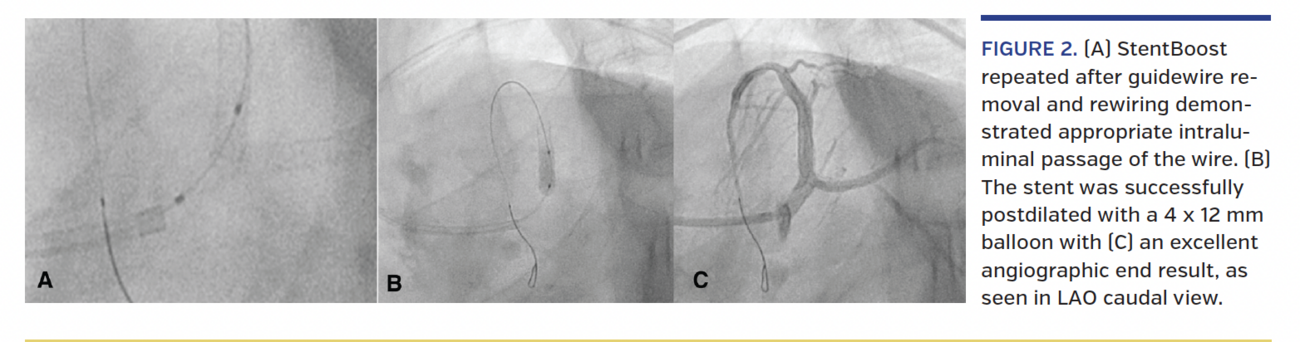

A 42-year-old hypertensive man presented to the emergency department with non-ST segment elevation myocardial infarction. Coronary angiogram revealed thrombotic occlusion of the first obtuse marginal (OM) branch and 70% eccentric stenosis of the proximal segment of left anterior descending (LAD) coronary artery (Figure 1A). He underwent successful percutaneous coronary intervention (PCI), with 2.5 x 28 mm Abluminus stent (Envision Scientific) deployed in the OM and 3.5 x 24 mm Abluminus stent deployed from the distal left main to the proximal LAD (Figure 1B). However, after rewiring of the LAD due to accidental guide disengagement, an attempt to postdilate the stent was unsuccessful, as two non-compliant balloons (4 mm and 3.5 mm) could not cross the stent. At this juncture, StentBoost (Philips Medical Systems) demonstrated abluminal passage of the guidewire through the proximal stent struts (Figure 1C and 1D). The coronary guidewire was removed, rewired and the stent postdilated (Figure 2B) with the same non-compliant balloon (4 x 12 mm) used previously with an excellent end result (Figure 2C) after StentBoost confirmed appropriate intraluminal passage of the coronary guidewire (Figure 2A).